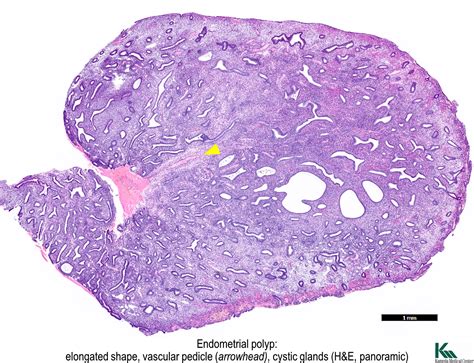

Weakly Proliferative Endometrium refers to a condition where the endometrium does not thicken adequately during the proliferative phase of the menstrual cycle. The proliferative phase is the first half of the menstrual cycle, during which the endometrium prepares for potential implantation of a fertilized egg. In a normal cycle, the endometrium thickens under the influence of estrogen. However, in cases of Weakly Proliferative Endometrium, this thickening is insufficient, which can impact fertility and overall reproductive health.

• Endometrial Biopsy: A small sample of the endometrium is taken for laboratory analysis to evaluate its structure and function.